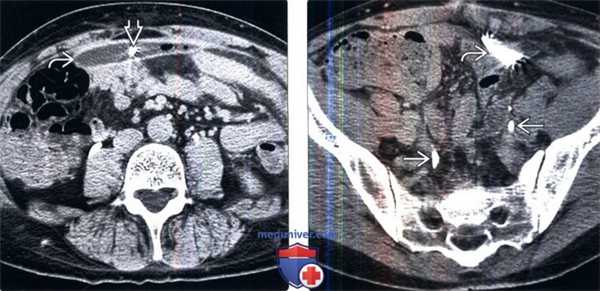

(Слева) КТ с контрастированием в экскреторную фазу после субтотальной колэктомии, аксиальный срез: экстравазация контрастируемой мочи в скопление жидкости вблизи места анастомоза ободочной кишки, вследствие пересечения мочеточника.

(Справа) Ретроградная пиелография: у этого же пациента определяется пересечение левого мочеточника и слабовыраженная экстравазация. На повторной операции было подтверждено пересечение мочеточника.